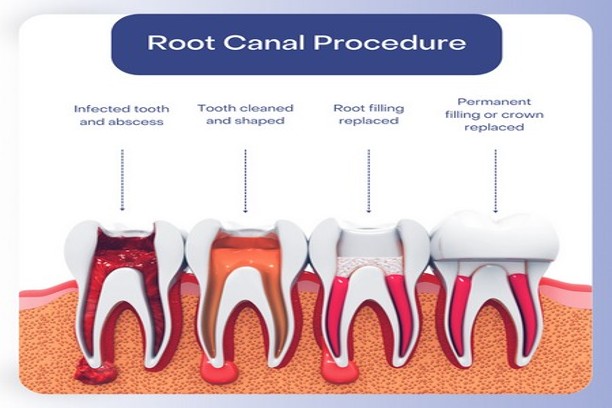

ROOTCANAL TREATMENT

ROOTCANAL TREATMENT